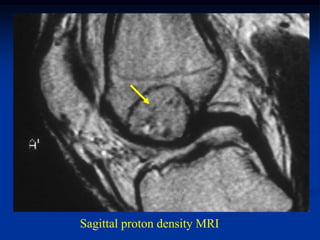

Case #121

17 year female

periosteal chondroma

distal femur

Bone scan

CT scan

Axial proton density MRI

Sagittal proton density MRI

Sagittal T-2 MRI

Photomic